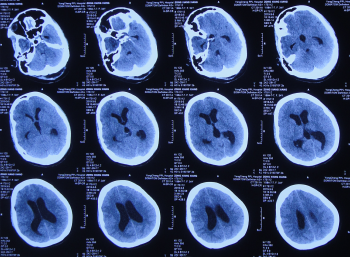

患者2019年2月初,因数次出现发作性黑蒙,2019年2月10日就诊于当地的河南省永城市某医院,查头颅CT未见明显异常(图-1);次日再查头颅核磁、颈椎核磁(图-2、图-3)后发现小脑扁桃体下疝畸形合并脊髓空洞。

图-2:2019年2月12日头颅核磁

图-3:2019年2月13日头颅核磁

小脑扁桃体下疝减压术后20天即2019年3月6日,查头颅、颈椎核磁发现仍有脊髓空洞(图-8、图-9)。

图-8:2019年3月6日头颅核磁

图-9:2019年3月6日头颅核磁